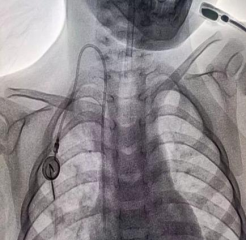

输液港植入术中操作情况

输液港植入术后情况及摄片情况